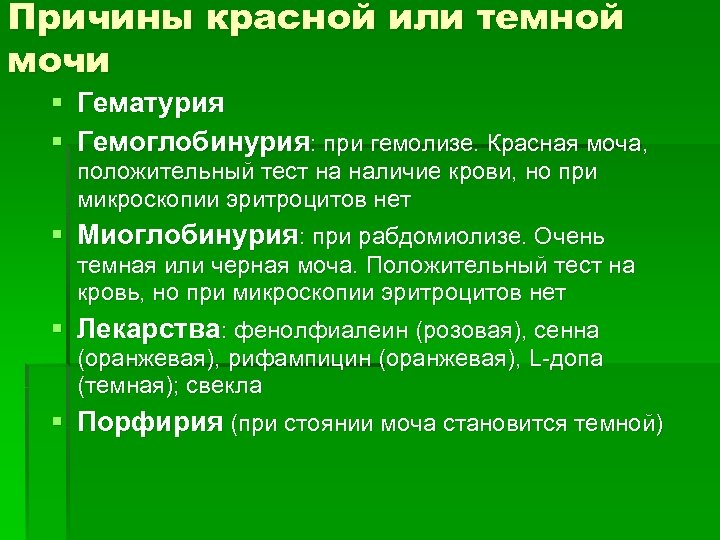

Причины красной или темной мочи § Гематурия § Гемоглобинурия: при гемолизе. Красная моча, положительный тест на наличие крови, но при микроскопии эритроцитов нет § Миоглобинурия: при рабдомиолизе. Очень темная или черная моча. Положительный тест на кровь, но при микроскопии эритроцитов нет § Лекарства: фенолфиалеин (pозовая), сенна (оранжевая), рифампицин (оранжевая), L-допа (темная); свекла § Порфирия (при стоянии моча становится темной)